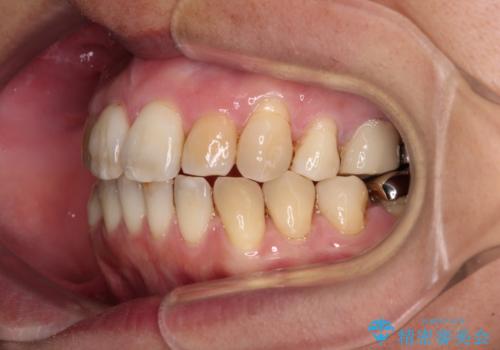

舌のトレーニングをしっかりと行ってくださり、10ヶ月で希望通りの歯列となりました。

日頃から飲まれる飲み物の影響で着色しやすいため、来院の度に着色除去のクリーニングも行っていました。